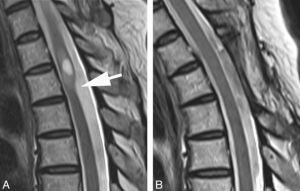

Arachnoid web deformities are most common in the thoracic spine and are diagnosed via a Sagittal MRI. They look for something called the scalpel sign where the distortion in the cord appears anteriorly displaced and resembles the profile of a surgical scalpel.